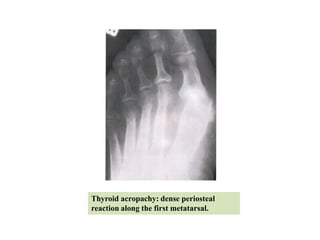

Thyroid acropachy

•It is a triad of pre-tibial myxoedema, exophthalmos &

clubbing of the fingers.

•Radiologically there is characteristic periosteal

thickening in the extremities; commonest &

characteristic site of involvement is the first metacarpal

or metatarsal.

Thyroid acropachy: dense periosteal

reaction along the first metatarsal.